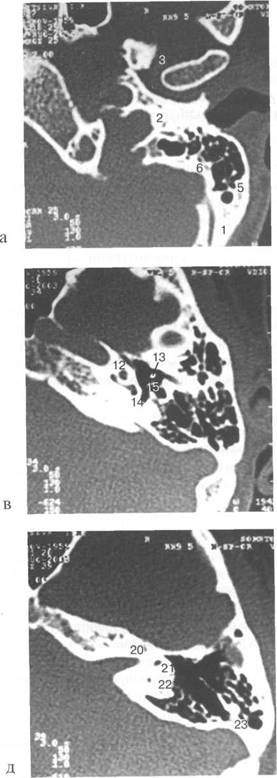

(mesotympanum), (epitympanum) (hypotympanum).

(adidus ad antrum), (attic) (m. stapedius).

(promontorium), (m. tensor tympani). (fenestra ovalis), (fenestra rotundum),

recessus epitympanicum, (tegmen tympani)

(antrum mastoideum), adidus ad antrum

«bone» «edge»

m. tensor tympani,

tegmen tympani,

L. VII VIII